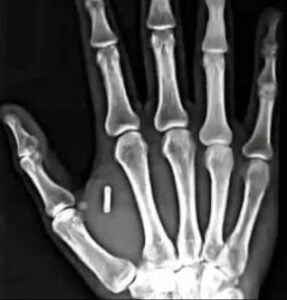

En Suède, une véritable révolution technologique est en marche : de plus en plus de citoyens choisissent volontairement de se faire implanter une puce électronique sous la peau, généralement entre le pouce et l’index. Ce petit dispositif, à peine plus grand qu’un grain de riz, contient une technologie NFC (Near Field Communication), la même que celle utilisée dans les cartes bancaires ou les téléphones pour les paiements sans contact.

L’initiative a vu le jour au milieu des années 2010, portée par des start-up comme Biohax International et Dsruptive Subdermals, qui ont vu dans cette innovation un moyen de simplifier le quotidien. En quelques années, plusieurs milliers de Suédois ont sauté le pas, souvent lors d’événements technologiques où les implants sont posés par des professionnels de santé en quelques secondes, sans anesthésie lourde.

En pratique, il suffit d’approcher la main d’un lecteur électronique pour que la puce transmette les données nécessaires.